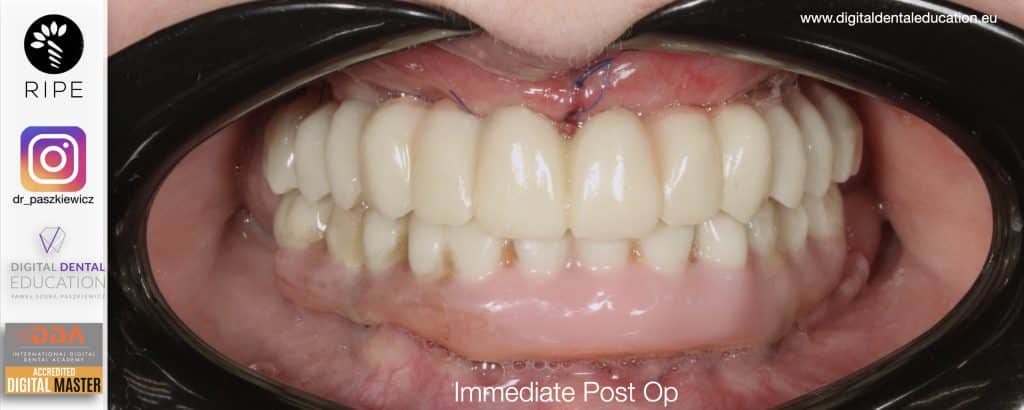

He has invented an AllonX non-impression protocol leading to final restorations post immediate implant full-arch loading, incorporated with desktop scanner (MEDIT) and ModJaw capturing of natural patient’s functional and mastication movements.